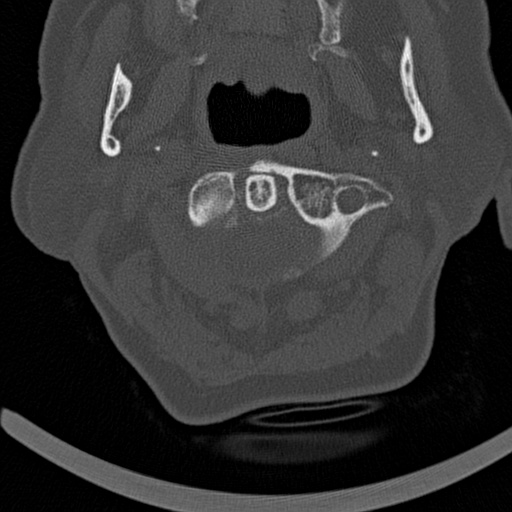

The primary dataset for this task is reasonably balanced, with a split of approximately 52% for non-fractured and 48% for fractured cases. Within the fractured cases, there is significant variability, with C7 having the highest proportion of fractures at 19%, while C3 exhibits the lowest incidence at 4%. It’s noteworthy that some patients may present with multiple fractures, which tend to occur in close proximity, such as between C4 and C5, rather than being dispersed across different vertebrae as shown in Figure 3. The medical image data is stored in Digital Imaging and Communications in Medicine (DICOM) format, a well-established standard for medical image storage. Information like image size, pixel dimensions, brightness, contrast, and pixel value range can be extracted from DICOM metadata, providing essential insights for image interpretation. Additionally, there are bounding boxes for a subset of the training data.

Overall The preprocessing phase for preparing images to be used in an image classification notebook is showcased by Algorithm 1, with selected outputs depicted in Figure 4.